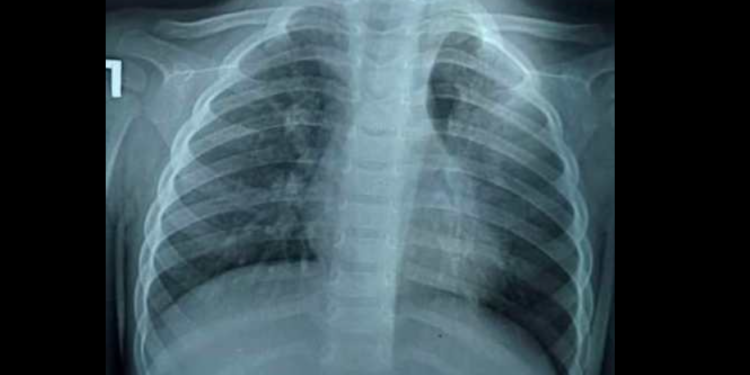

Бишкекте 1 жаш 10 айлык баланын өпкөсүнөн жүгөрүнүн даны табылганын балдар хирургу Калыбек Мыкиев социалдык тармактагы баракчасында билдирди.

«Ата-энелердин эсине! Өзгөчө кичине балдары барларга! 3 айдан бери ар кайсы жакта дарыланышкан, көп антибиотик алышкан, акырында бүгүн 14-июлда бронхоскопия жасап сол бронхтон жүгөрү алып чыктык. Толтура ириң кан. Дагы жасалышы мүмкүн. Дагы 3-4 ай жүргөндө сол өпкө жарабай калмак. Балдарга көз салгыла, ата-энелер»,— деп жазды ал.